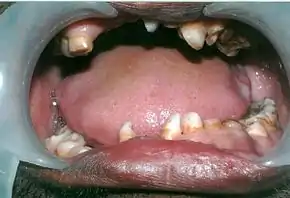

Panoramic view of the jaws showing multiple unerupted supernumerary teeth mimicking premolar, missing gonial angles and underdeveloped maxillary sinuses in cleidocranial dysplasia.

- The permanent teeth include supernumerary teeth. Unless these supernumeraries are removed they will crowd the adult teeth in what already may be an underdeveloped jaw. If so, the supernumeraries will probably need to be removed to make space for the adult teeth. Up to 13 supernumerary teeth have been observed. Teeth may also be displaced. Cementum formation may be deficient.[13]

- Failure of eruption of permanent teeth.